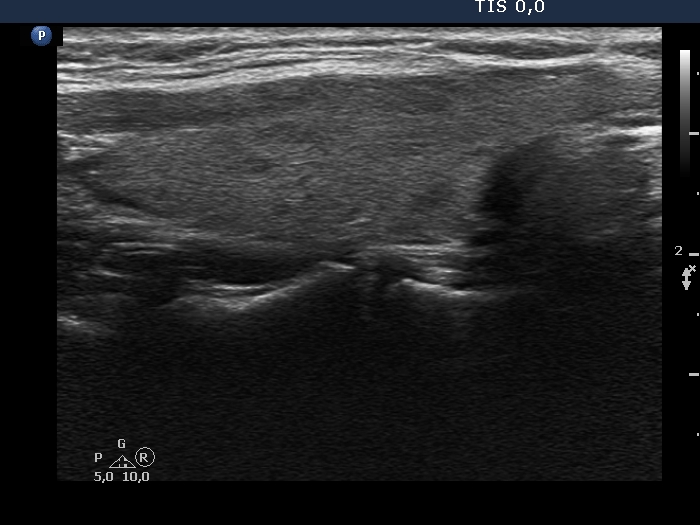

100 consecutive cases of papillary cancer - case 089 (ultrasonographic picture 2)

Right lobe, longitudinal scan.